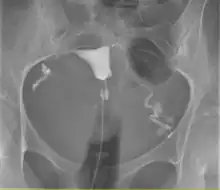

Histerosalpingografia é um exame de raio-x do útero e das trompas uterinas, com a utilização de contraste iodado que é injetado no interior do útero através de uma cânula. Serve para diagnosticar malformações, doenças da cavidade uterina e do interior das trompas. Sua principal indicação está correlacionada com a infertilidade e é o melhor método[carece de fontes] para diagnosticar obstrução das trompas.

Uma histerossalpingograma normal. Observe o cateter entrando pela parte inferior da tela e o meio de contraste preenchendo a cavidade uterina (pequeno triângulo no centro).